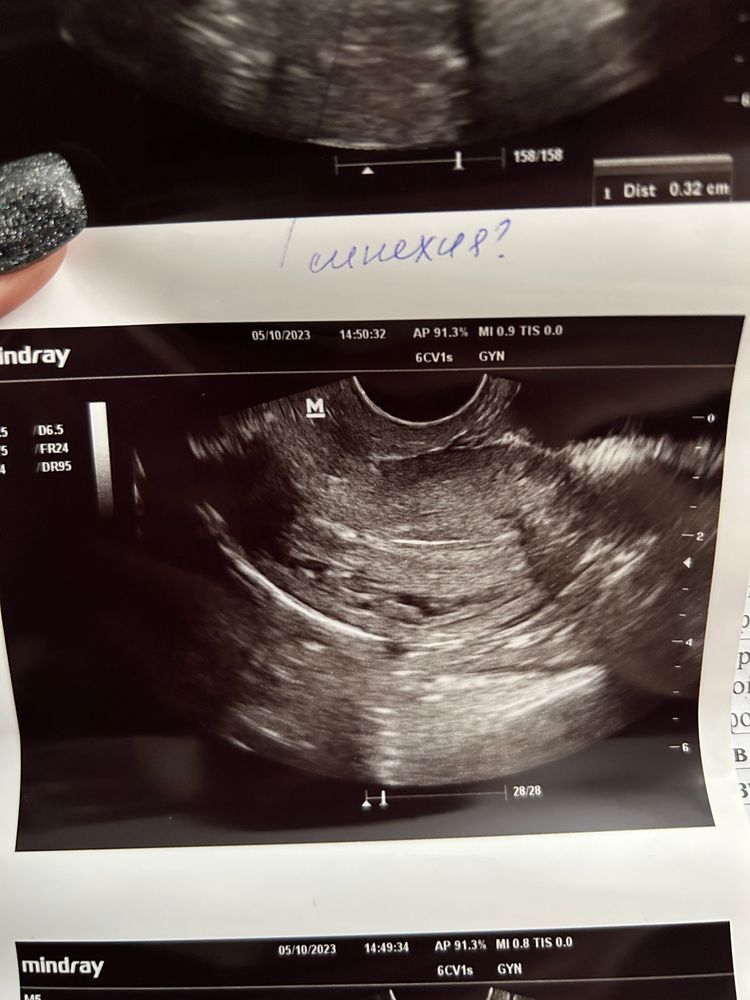

Синехия? Фото узи прилагаю

Ходила сегодня на фолликулометрию, и обнаружили вот это. Врач сказала, что это либо резец от давней чистки, ибо была ЗБ (синехия), либо так выглядит моя матка и предположила, что она седловидная. У кого такое было? Поделитесь

У меня синехия выглядела так.

Было ощущение, что полоска смыкания эндометрия прерывается и потом опять появляется.